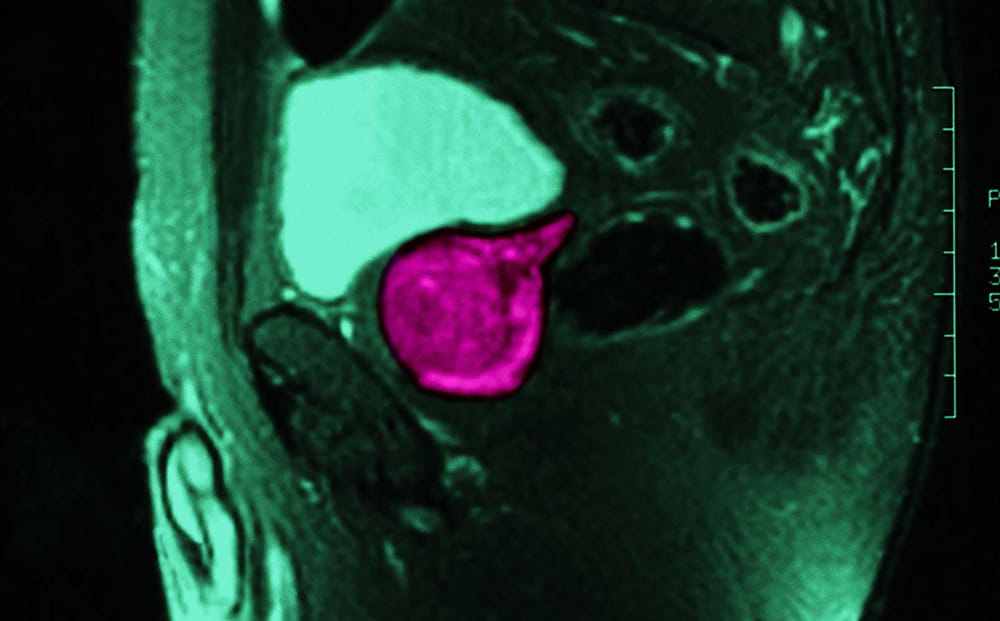

Supported by a National Institutes of Health (NIH) grant, our team played an important role in a unique discovery that is now available to patients at University across Northeast Ohio. Dr. Lee Ponsky and his team developed a combined quantitative MRI and computerized decision support exam for more accurate detection and grading of prostate cancer both in the peripheral and transitional zones. It’s just one of the ways University Hospitals is researching, developing and delivering new and advanced patient care with these MRIs for prostate cancer screening.